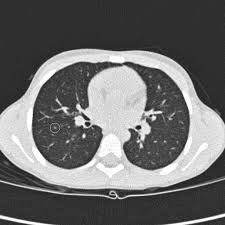

Getting checked early for lung cancer is. Sometimes, a nodule can be an early lung cancer. Secondhand smoke causes lung cancer in adults who have never smoked. Richard mario lurshay medically reviewed by dr. Around 44,500 people are diagnosed with the condition every year in the uk.